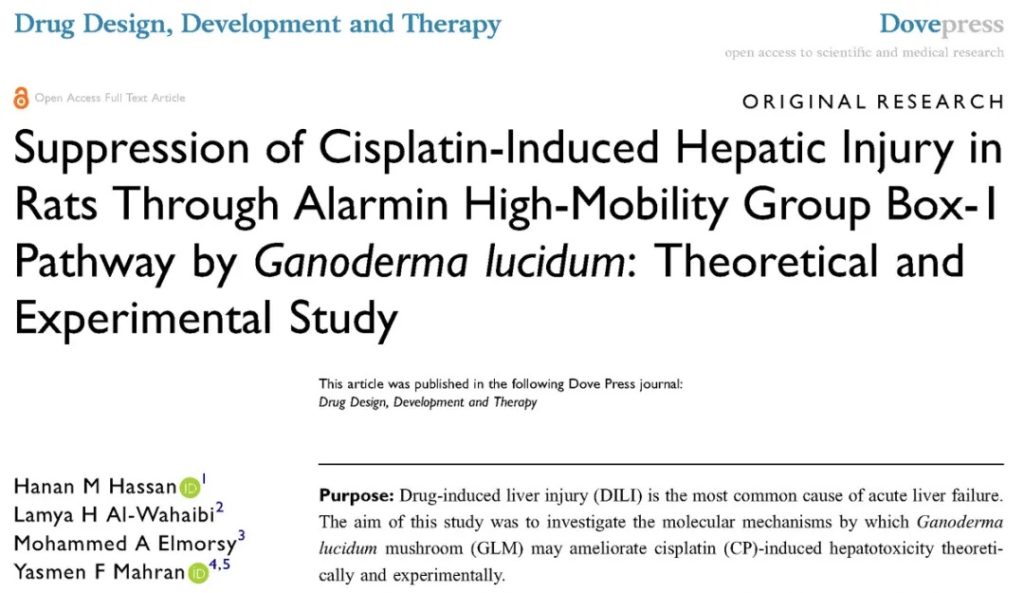

A team composed of Professor Hanan M Hassan from the Faculty of Pharmacy of Delta University for Science & Technology in Egypt and Professor Yasmen F Mahran from the Faculty of Pharmacy of Ain Shams University in Egypt used cisplatin, the most common traditional chemotherapy drug, to test the possibility of Ganoderma lucidum in protecting liver and kidney cells from cisplatin injury.

Their research results are divided into two articles: one is protecting the liver while another is protecting the kidneys. They were published in “Drug Design, Development and Therapy” and “Oxidative Medicine and Cellular Longevity” in June and July 2020, respectively.

Part 1 Ganoderma lucidum protects the liver vs. cisplatin hepatotoxicity

The researchers compared the differences between using and not using Ganoderma lucidum during cisplatin treatment in six groups of healthy rats and the differences in protection against liver injury with different Ganoderma lucidum administration methods. They are: